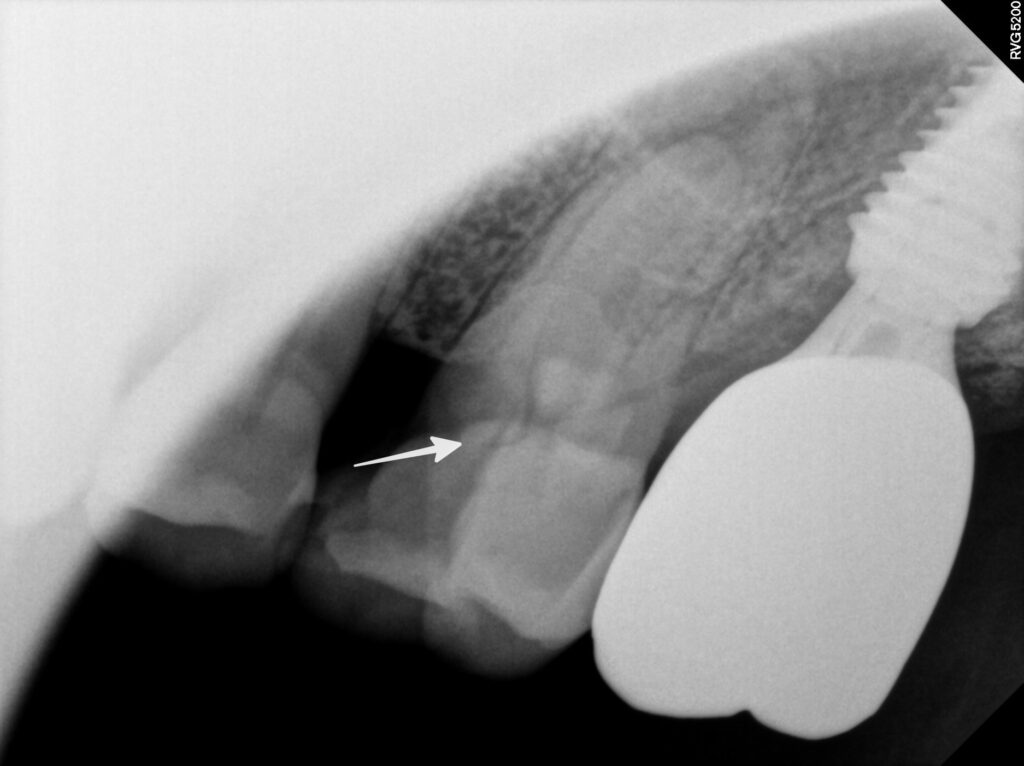

X-ray 검사를 통해

파절 범위와 치아 뿌리의 상태를

면밀히 살펴본 결과

신경치료가 필요한 상태로 판단됩니다.